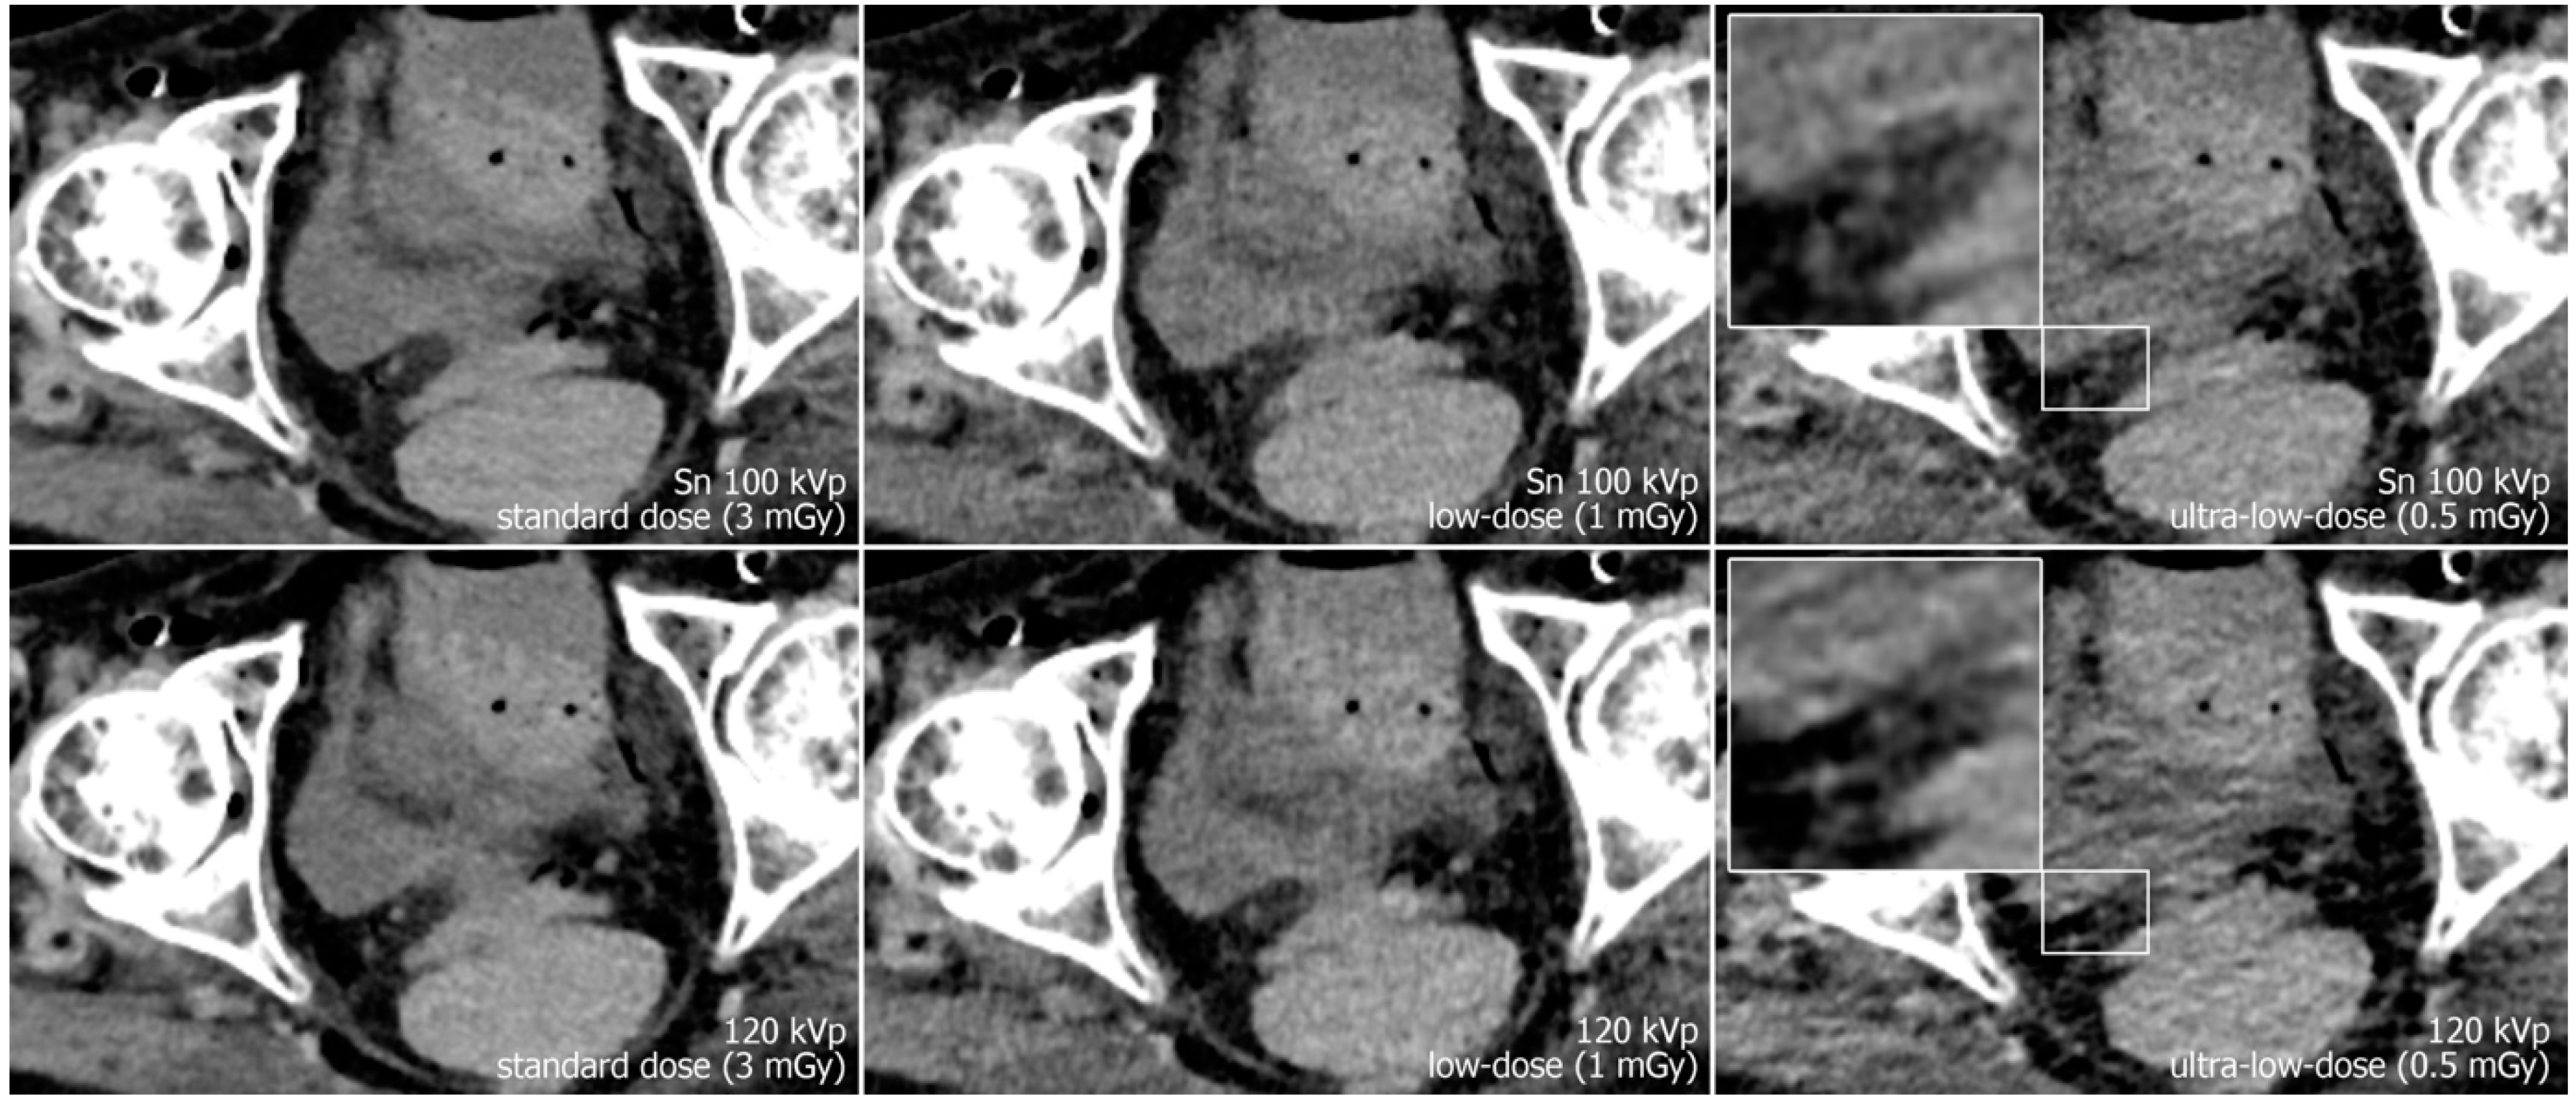

Reconstruction of datasets followed identical parameters: slice thickness and increment were set to 3 mm each, and the field of view to 400 mm with a 512 × 512 pixel matrix. A soft tissue convolution kernel (Br36) was applied with the highest strength level of a dedicated quantum iterative reconstruction algorithm (QIR 4). For polychromatic scans, “T3D” mode was enabled, which includes photon energies between 20 and 120 keV [29]. Window settings were pre-set to 300/40 Hounsfield units (width/center) were employed for dedicated analysis of soft tissue. However, readers were given the possibility to adjust these settings at will during image quality assessment. Examples regarding differences in image quality of the pelvic region between acquisition protocols are provided in Figure 1, while Figure 2 illustrates the encumbered demarcability of the lower Ureter in ultra-low-dose scans.

Figure 1.

Axial view of the left distal ureter (arrow). Note the impaired image quality due to hypodense streak artifacts in polychromatic scans at 120 kVp (lower row), especially with ultra-low radiation dose. (The arrow marks the left ureter with an adjacent phlebolite.)

Figure 2.

Axial view of the right distal ureter (magnification) in a different specimen. Again, the image quality is reduced and demarcability of the ureter is impaired, especially in ultra-low-dose polychromatic imaging compared to the dose-matched protocol with tin filtration.